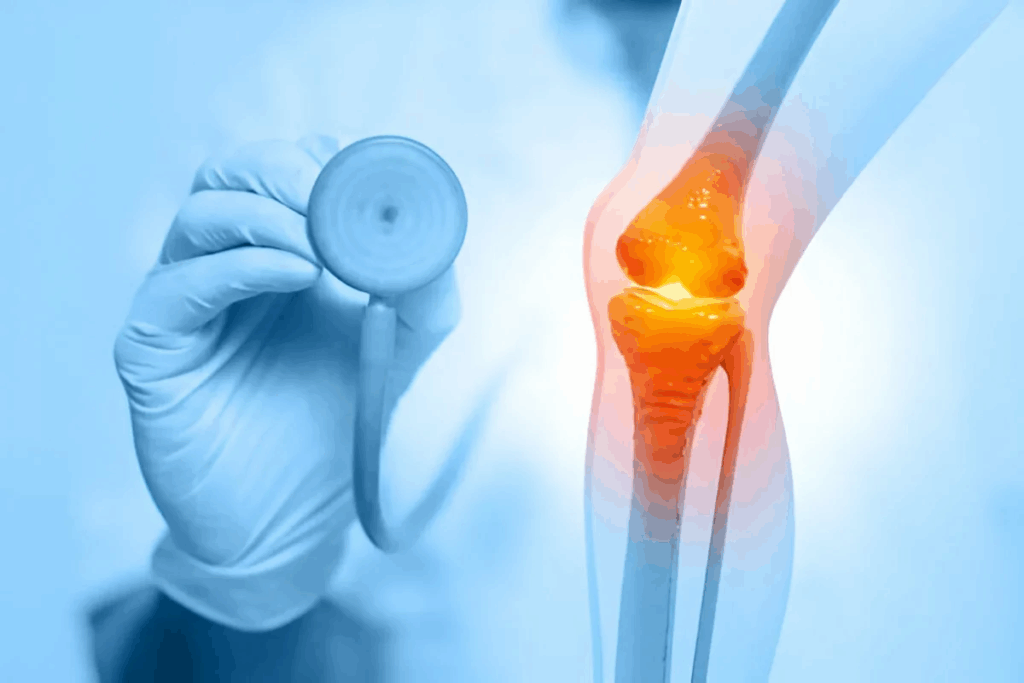

Rheumatoid Arthritis Exacerbations

Rheumatoid arthritis causes joint inflammation, leading to pain, swelling, and damage. Flare-ups can make joints hurt more, feel stiffer, and move less. They can be triggered by stress, infections, or changes in medication.

- Increased joint pain and swelling

- Reduced mobility and stiffness

- Systemic symptoms like fever and fatigue